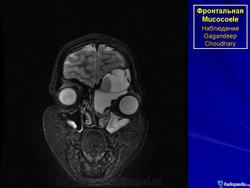

Мукоцеле

Приложения:

1.mu_.slayd364.jpg2.mu_.slayd365.jpg3.mu_.slayd366.jpg